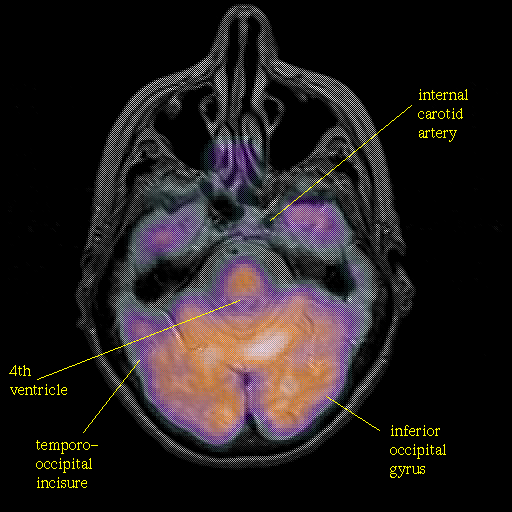

overlay : Slice 16

Slice 16